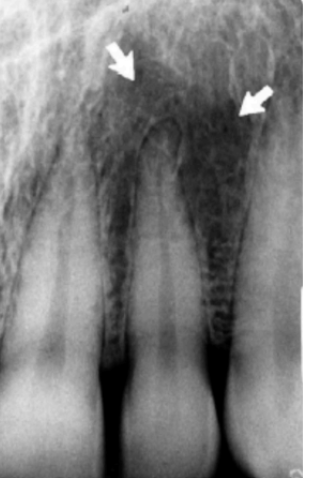

list 3 things that show the periodontal status of a tooth

crown:root ratio

verticla bone loss

horizontal bone loss

what type

HBL